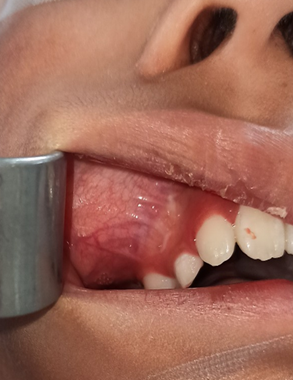

Se decide realizar una biopsia incisional intraoral de dicha lesión bajo anestesia general (Figura 4), el cual reportó fibroma osificante juvenil, por lo que se decidió realizar una maxilectomia parcial con preservación de piso de orbita, con un abordaje intraoral (Figura 5A-D).

Figura 4 Biopsia incisional con abordaje intraoral.